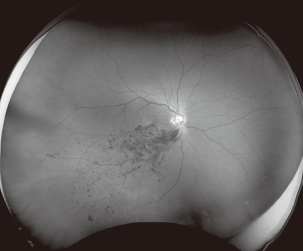

超广角视网膜成像

2、单次成像200°眼底范围。欧堡一次成像可反映大于80%的视网膜情况,可以帮助医生更高效的发现和诊断视网膜疾病,检查出更多眼底问题。结合眼位引导范围可达到220°~240°

4、多种成像模式,视网膜、脉络膜成像更清晰,满足不同临床需求。